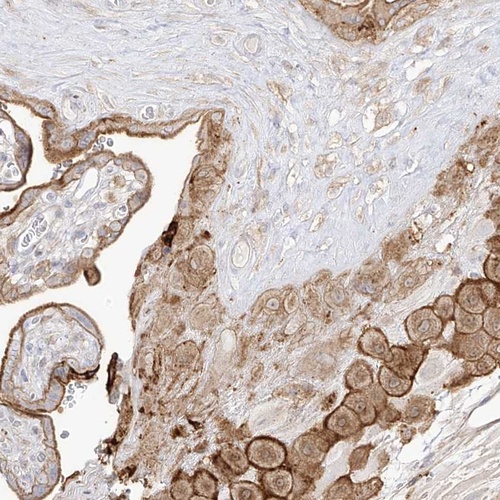

Immunohistochemical staining of human placenta shows moderate cytoplasmic and membranous positivity in decidual and trophoblastic cells.